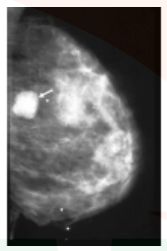

The following imaging on mammography represents a _____

Most important sign of malignancy in mammogram is _____ micro calcification

Hint: diffuse/clustered